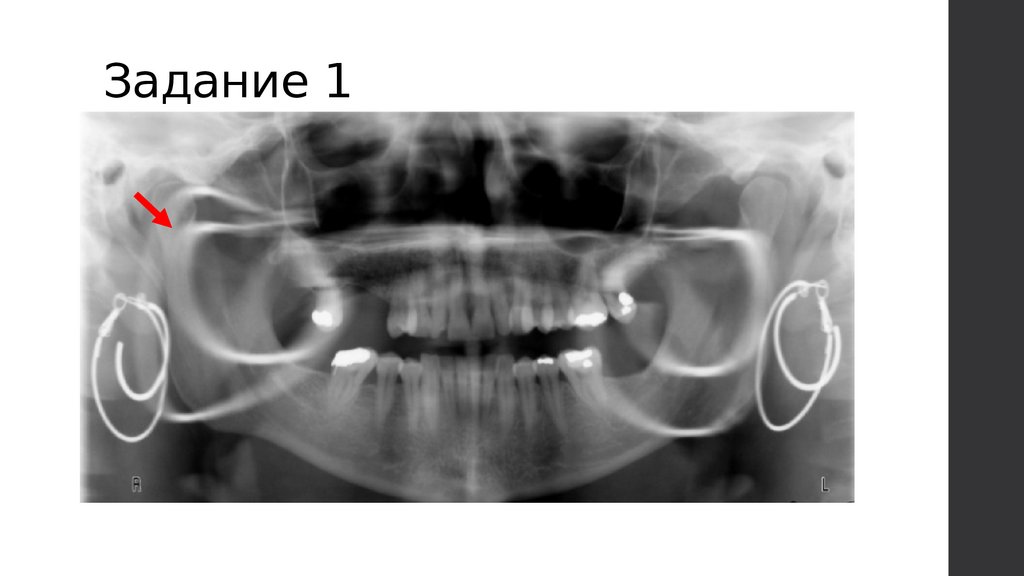

Задание 1

39.

Инородные предметы на

панорамном снимке